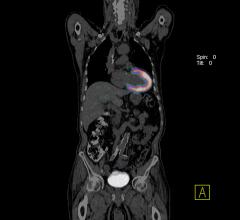

Positron emission tomography (PET) is a nuclear imaging technology (also referred to as molecular imaging) that enables visualization of metabolic processes in the body. The basics of PET imaging is that the technique detects pairs of gamma rays emitted indirectly by a positron-emitting radionuclide (also called radiopharmaceuticals, radionuclides or radiotracer). The tracer is injected into a vein on a biologically active molecule, usually a sugar that is used for cellular energy. PET systems have sensitive detector panels to capture gamma ray emissions from inside the body and use software to plot to triangulate the source of the emissions, creating 3-D computed tomography images of the tracer concentrations within the body.